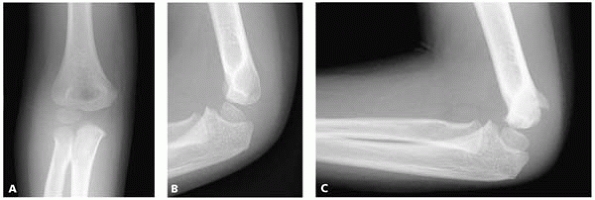

▪ FIGURE 6-2 A:

Type A fracture. Fracture through the lateral humeral condyle with a minimal gap laterally. The fracture cannot be followed to the epiphyseal cartilage. B: Outline of the radiograph. (Reprinted with permission from Finnbogason T, Karlsson G, Lindberg L, et al. Nondisplaced and minimally displaced fractures of the lateral humeral condyle in children: a prospective radiographic investigation of fracture stability. J Pediatr Orthop. 1995;15(4):422-425.) |

▪ FIGURE 6-3 A:

Type B fracture. Fracture through the lateral humeral condyle with a gap laterally. The fracture can be followed to the epiphyseal cartilage. B: Outline of the radiograph. (Reprinted with permission from Finnbogason T, Karlsson G, Lindberg L, et al. Nondisplaced and minimally displaced fractures of the lateral humeral condyle in children: a prospective radiographic investigation of fracture stability. J Pediatr Orthop. 1995;5(4):422-425.) |

▪ FIGURE 6-4 A: Type C fracture. Fracture through the lateral humeral condyle. The fracture gap is as wide laterally as medially. B:

Outline of the radiograph. (Reprinted with permission from Finnbogason T, Karlsson G, Lindberg L, et al. Nondisplaced and minimally displaced fractures of the lateral humeral condyle in children: a prospective radiographic investigation of fracture stability. J Pediatr Orthop. 1995;15(4):422-425.) |

the fracture is stable and not at risk for displacement1 (Fig. 6-2).

However, when the fracture line extended into the epiphysis, with the

lateral gap greater than the medial gap, 17% (6/35) of fractures

displaced (Fig. 6-3). When the fracture gap at the epiphysis was equal to the lateral gap, 42% (5/12) of fractures displaced (Fig. 6-4).